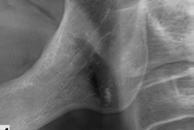

En la ortopantomografía se aprecia una dentición permanente a falta de la erupción de los 2os y 3 os molares, así como una asimetría ósea con rama y cóndilo mandibular izquierdo menos desarrollado (figura 9), causante de la asimetría facial descrita anteriormente.

Figuras 9-11.